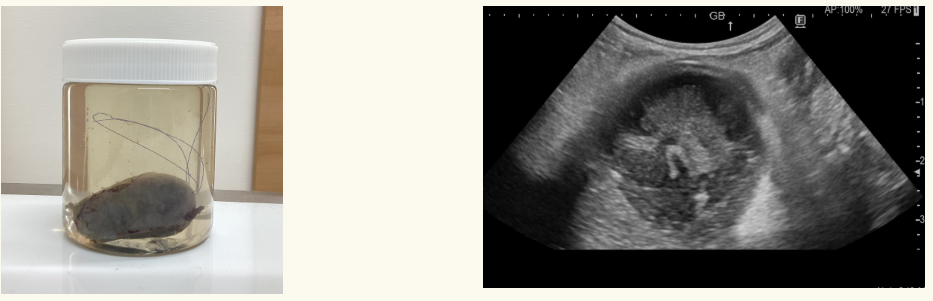

上記のエコー画像は冒頭の胆嚢摘出した症例の手術9か月前のエコー画像です。2枚とも同日です。

そんなに量は多くありませんが、胆嚢壁にはりつくような胆泥「重力非依存性胆泥」を認めます。

胆泥は①重力依存性胆泥 と ②重力非依存性胆泥 に分けて考えます。

①は重力方向に動くということです。

立位でエコーを見ると重力に従い腹側に溜まっていた胆泥が、仰向けにすると重力に従い背側に移動するなら重力依存性胆泥です。流動性胆泥とか可動性胆泥とか言われたら同じ意味です。

これを異常所見とすると、高齢犬の大半は異常になってしまいます。重力依存性胆泥にウルソを処方し続けることを当院では推奨していません。

問題は②です。

重力によって動かない壁にはりついたような胆泥です。これがある子がみんな粘液嚢腫化するかというと、そんなことはないと思います。ただ、①よりはリスクが高い状態と言えると思います。

今回このような症例を経験させていただいたので、当院では重力非依存性胆泥を認めた場合には、エビデンスは乏しいことを説明した上で、しかしながら、もし胆嚢粘液嚢腫になってしまうと命に関わるので少しでも可能性を下げたいとご希望いただけるのであれば、飼い主様に無理のない範囲での予防策をご提案するようにしようと思います。